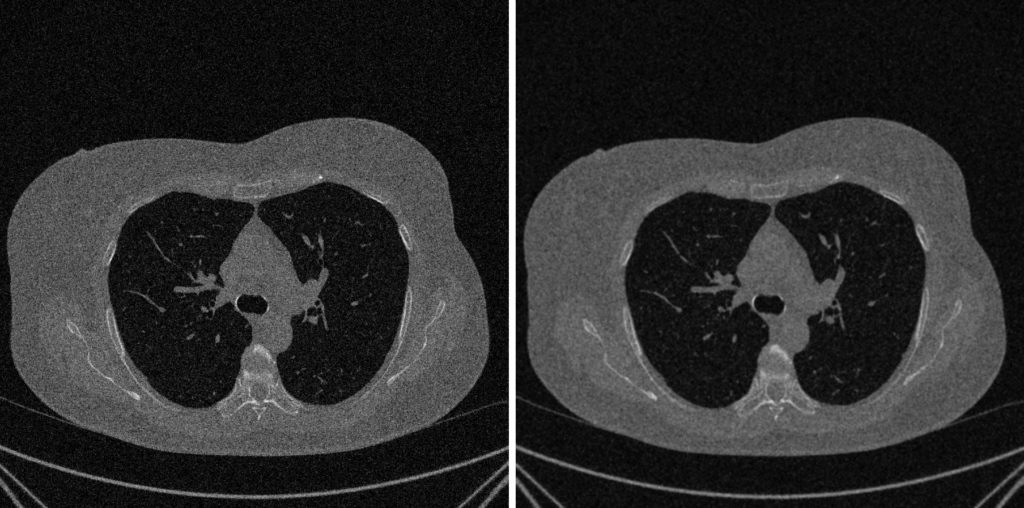

4. Fase 3: Denoising e Sharpening

Dopo aver corretto gli artefatti sistematici, l’immagine è corretta, ma non ancora pulita. Può essere ancora affetta da rumore casuale (elettronico o statistico), che oscura i dettagli fini e complica le analisi successive come la segmentazione.

Esploriamo ora due operazioni complementari e in apparente conflitto: il Denoising (ridurre il rumore) e lo Sharpening (evidenziare i bordi).

1. Denoising: Smussare il Rumore, Preservare il Segnale

L’obiettivo è sopprimere il rumore senza distruggere i bordi e le texture reali dell’immagine.

Filtri Edge-Preserving

- Filtro Bilaterale è un miglioramento sofisticato del filtro Gaussiano che utilizza una media pesata basata su due criteri fondamental: La Vicinanza Spazialeper cui i pixel più vicini al centro del calcolo ricevono un peso maggiore e la Somiglianza di Intensità dove I pixel con un valore cromatico o di intensità simile ricevono anch’essi un peso maggiore

- Pro: Conservazione dei Bordi e Qualità Visiva Superiore

- Contro: Complessità Computazionale; Selezione dei Parametri per il dominio spaziale e uno per il dominio di intensità può richiedere tentativi ed errori per ottimizzare il risultato; Introduzione di Artefatti se i parametri non sono scelti correttamente.

- Non-Local Means (NLM): Sfrutta la ridondanza presente nell’immagine per il denoising. Per pulire un pixel, cerca “patch” simili in tutta l’immagine (approccio non-locale), non limitandosi all’area circostante. Il nuovo valore del pixel è una media pesata dei pixel centrali di tutte le patch simili trovate.

- Pro: Denoising eccellente preservando le texture fini.

- Contro: Alta complessità computazionale e lentezza.

- Wavelet Denoising: Scompone l’immagine in diverse frequenze di dettaglio. L’immagine viene scomposta in coefficienti nel dominio wavelet. I coefficienti deboli (associati a rumore, basse frequenze) vengono azzerati o ridotti (soft-thresholding), mentre quelli forti (bordi, alte frequenze) vengono preservati. L’immagine viene poi ricostruita.

- Pro: Eccezionale sul rumore additivo gaussiano, preserva benissimo i dettagli (bordi netti).

- Contro: Può introdurre artefatti visivi se la soglia (threshold) non è impostata correttamente. Computationalmente più pesante rispetto a filtri semplici come il filtro media.